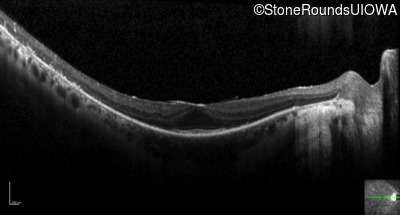

Optical Coherence Tomography - Right - 20/20

Exemplar / OCT Stack

OCT Stack